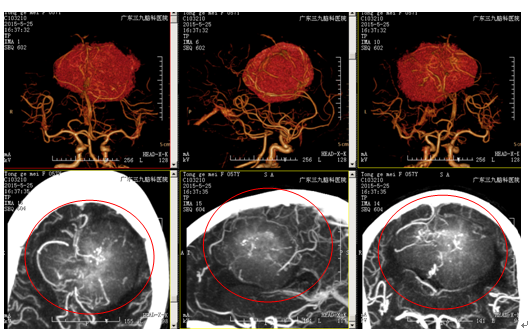

检查:颅脑CT及MR提示大脑镰前部游离缘两旁(左侧为主)巨大占位性病变,血供极其丰富,大小约8.0cm×7.0cm×5.3cm,考虑脑膜瘤可能性大。

诊断:双侧大脑镰旁巨大占位性病变(脑膜瘤可能性大)